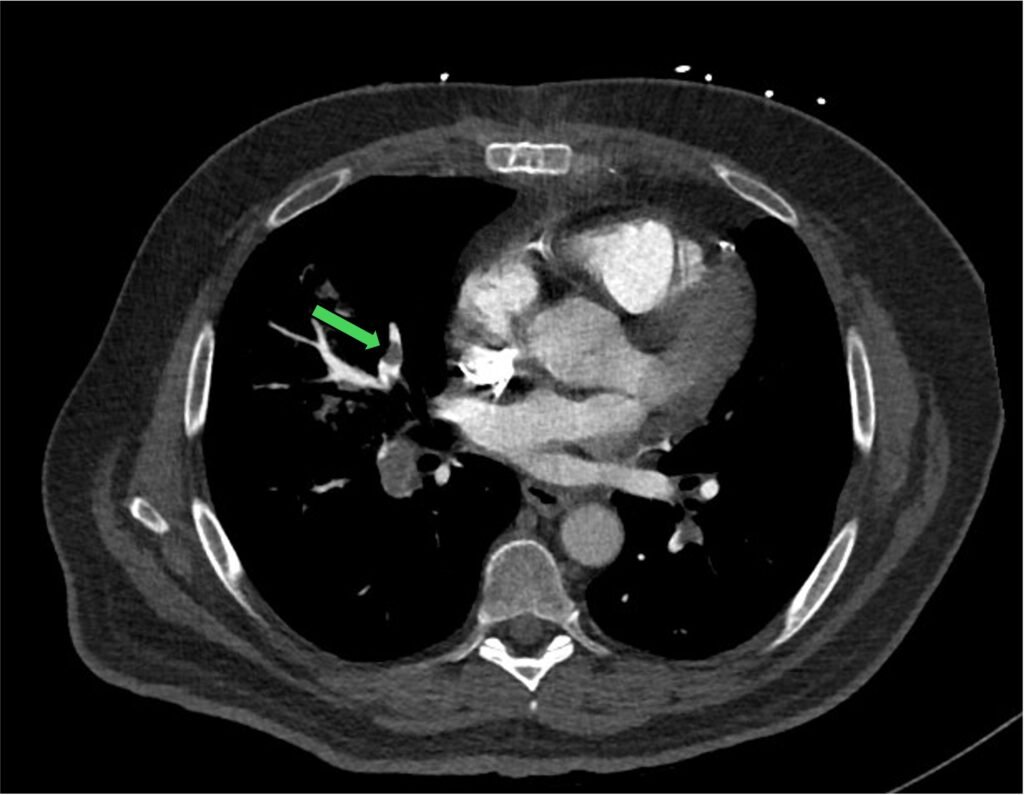

Figure 3: pulmonary trunk (green arrow) with bifurcation to left and right main PA

In this situation, it does help to be familiar with the PA anatomy and its branches. Below is the crude schematic diagram of the main PA and its branches.